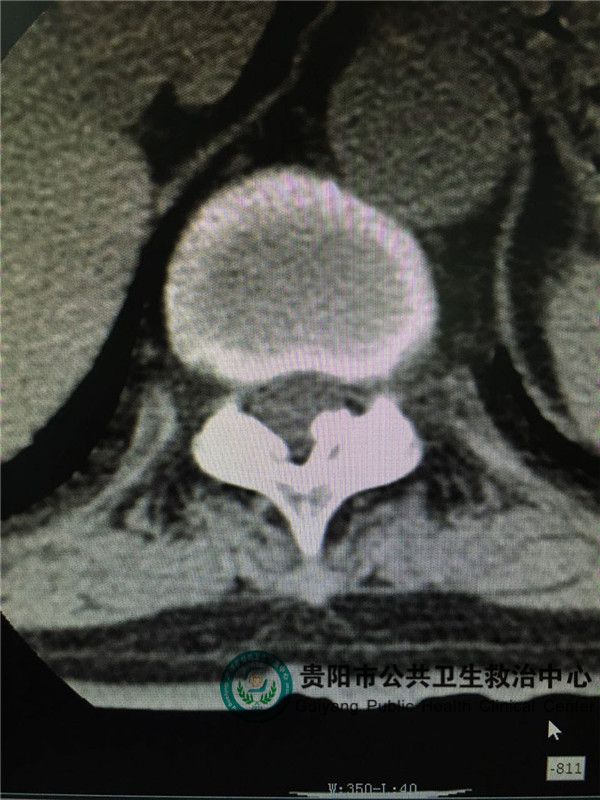

圖2

圖2,圖3,圖4是胸椎病灶節(jié)段CT平掃,可見(jiàn)椎管左側(cè)有占位壓迫脊髓,椎管明顯變窄。和患者體征相符。